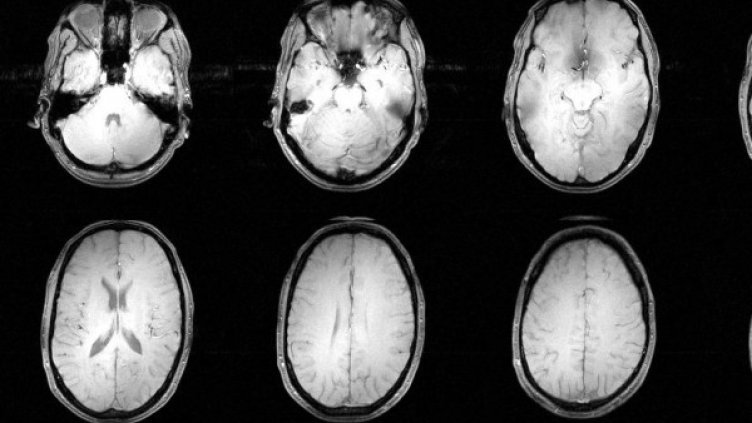

Процедурата носи името крионика. "Пациентите", които са избрали да не бъдат погребани в студената земя, се съхраняват в контейнери, пълни с азот, при температура от - 196 градуса. Това са градусите, при които жизнени, химични и като цяло всички процеси спират. На -196 градуса, времето вече не тече.

За да бъде съхранено едно тяло, то трябва да бъде "обработено" в рамките на 48 часа след настъпилата смърт. Първо, кръвта се заменя със субстанция, за да не бъдат повредени клетките, когато замръзнат. След това "пациентът" се потопявя в лед и се полага в контейнер с азот, където да чака развитието на технологиите.